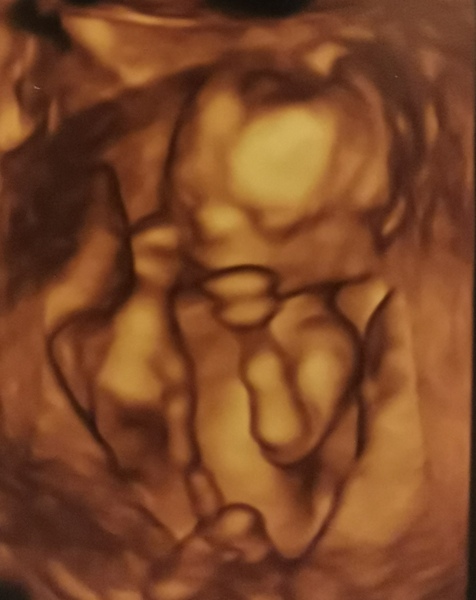

A little update from me, scan went really well today, we're having another little girl 😍💕

That’s great news @Busybee143 massive congratulations to you and DW. Beautiful baby yoda 😍😍

Congrats @Busybee143 ! Looks like she'll be coming out boxing lol